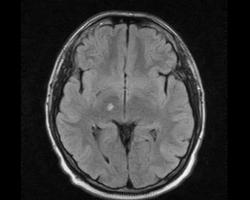

М, 27 лет. Жалобы на головные боли. ЧМТ в анамнезе. Стационар выставил внутримозговую гематому по КТ, полечили, отпустили.  К нам пришел на контроль.

Локализация таламус, граница коркового/мозгового, похоже на множественные кавернозные ангиомы. То, что в левой лобной?

Хочу посоветоваться с коллегами).  Дифференциальный ряд построить. Например токсоплазмоз, метастазы....в общем жду.

Сложно представить у молодого человека и каверномы, и метастазы одновременно.

Наверное, все же множественные каверномы, слева -осложненная кровоизлиянием.

Еще спросить хотел та что осложненная кровоизлиянием. Кровь хроническая тут?

Пришел к выводу, что сдесь все таки не каврномы, а мелкоочаговые кровоизлияния (ДАП). Учитывая травму и пребывание после этого  пациента в коме.